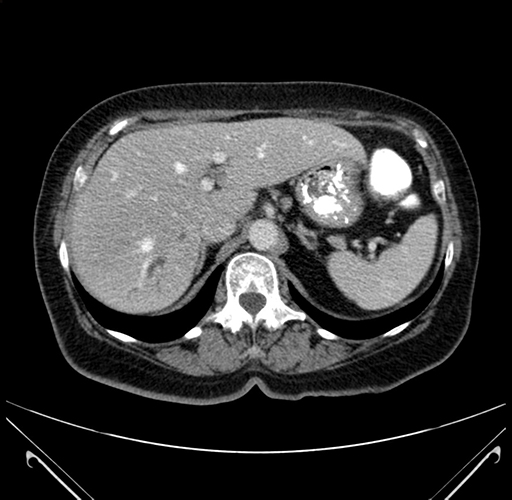

Axial Venous